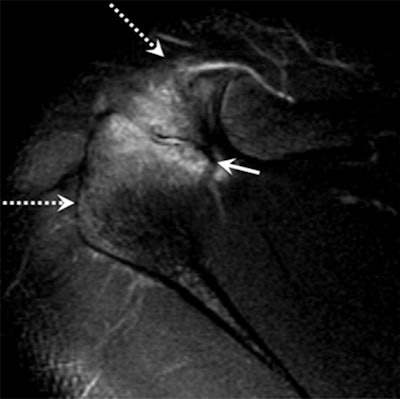

Image above shows incomplete fusion with moderate bone marrow edema in an 18-year-old male pitcher with acromial apophysiolysis. MR image below in the same patient at age 25 after quitting pitching shows complete fusion and resolution of the previously seen acromial edema (dashed arrows). Images courtesy of Radiology.

"The two findings with MRI that make the diagnosis for us are bone marrow edema, and the fusion with the two bones of the acromion still has to be open," he said. "You can see the nonfusion [of the acromion bones] on other modalities, such as CT and x-ray, but the edema is something you cannot pick up on any other imaging modality than MRI. So MRI is necessary to make the diagnosis and cannot be replaced by any other modality, because the edema is half of the diagnosis. You definitely need to see the edema."